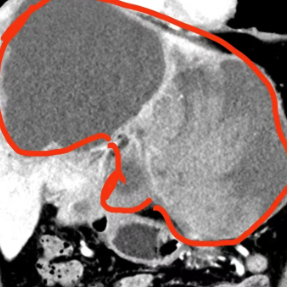

影像资料显示:巨大的肿瘤占据了刘先生整个肝脏的三分之二

湖南省人民医院专家团队为刘先生进行了多学科会诊。专家团队一致认为:巨大的肿瘤占据了患者整个左肝以及右肝前叶,手术操作空间极为狭小;加上肿瘤内部出血超过2000毫升,面对血供如此丰富的肿瘤,手术操作必须十分精准,否则极可能引发术中大出血,甚至危及生命;此外,在术前的下肢深静脉血栓筛查中,患者被发现有右下肢静脉血栓。